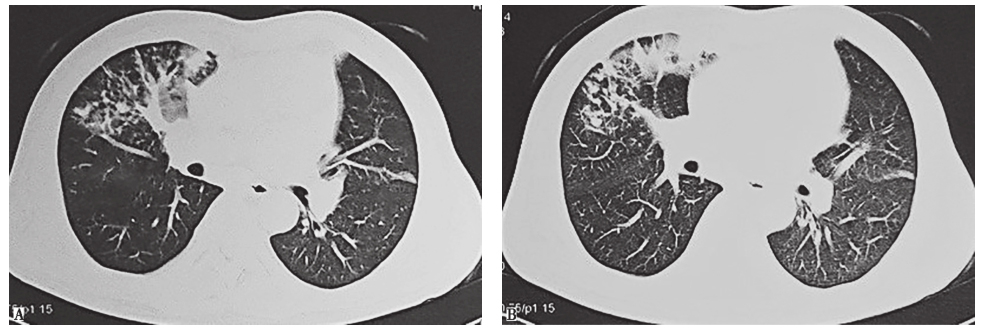

入院前两次胸部CT表现见图1、图2。

图1 发病第20天胸部CT表现

胸部CT可见双肺片状高密度影及多发空洞形成,伴右肺中叶膨胀不全

图2 发病第32天胸部CT表现

胸部CT可见右肺中叶区不张,左肺上叶原空洞部位出现部分实变